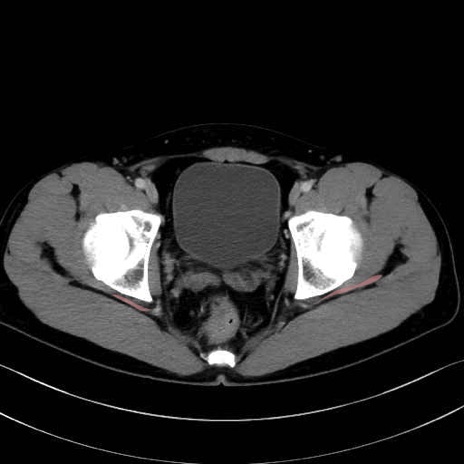

梨状筋(piriformis muscle) のCT画像の解剖

梨状筋 (Piriformis)